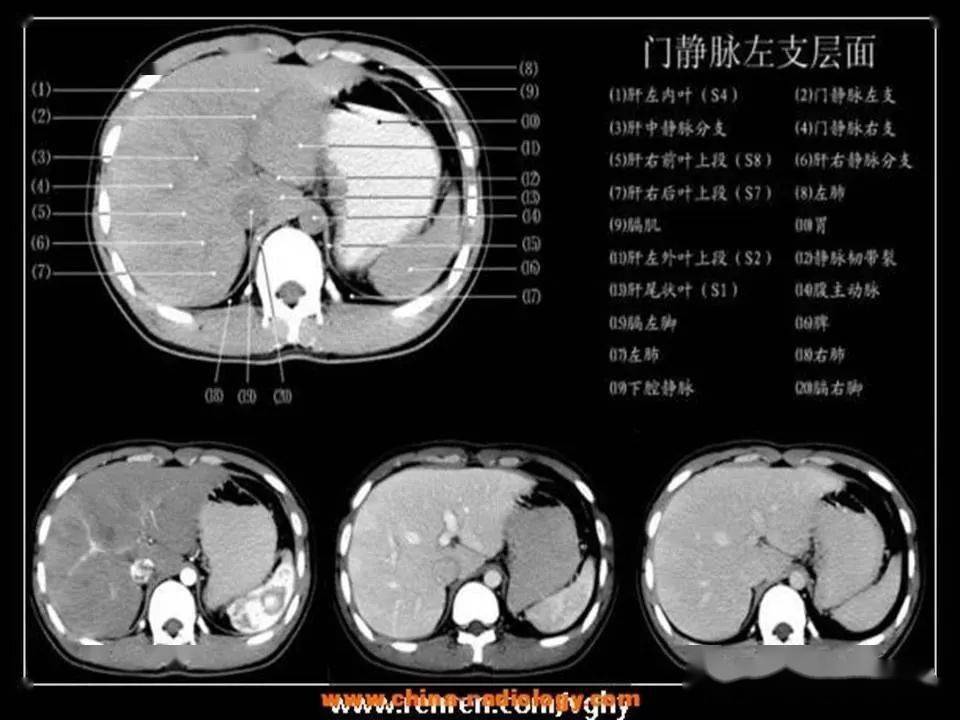

「腹部ct断层解剖」腹部ct扫描横断位解剖 详细标注,值得收藏

腹部ct入门解剖图谱收藏版